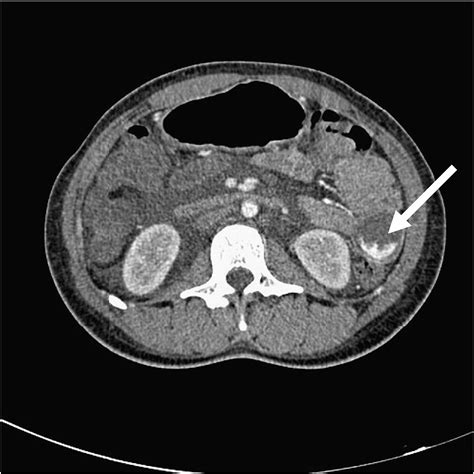

When a physician investigates an unusual lesion, they employ various diagnostic tools to gain a clearer picture of the pathology. This process is vital to differentiate a Dieu La Foy Lesion from other common skin issues like hemangiomas, angiomas, or simple vascular malformations. The standard approach includes:

• Imaging: In cases where the lesion appears deep or vascular in nature, ultrasound or MRI may be used to assess the underlying involvement of blood vessels.